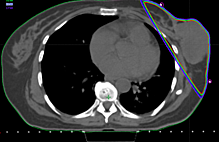

This 58-year-old woman had deep and aching post-mastectomy pain after mastectomy and chemotherapy, which was sharp where the circles are noted in Figure 2, for almost a year. Her pain was 10/10 before treatment; she obtained relief during treatment and her pain decreased to 0-1/10 after two 45-minute treatments. Her pain returned one month later; three treatments reduced her pain from 4/10 to 0/10, which lasted for several months. She noted, as did Patient 1, a marked improvement in her quality of life. She continues on single intermittent treatments every 30-90 days (Figure 2).